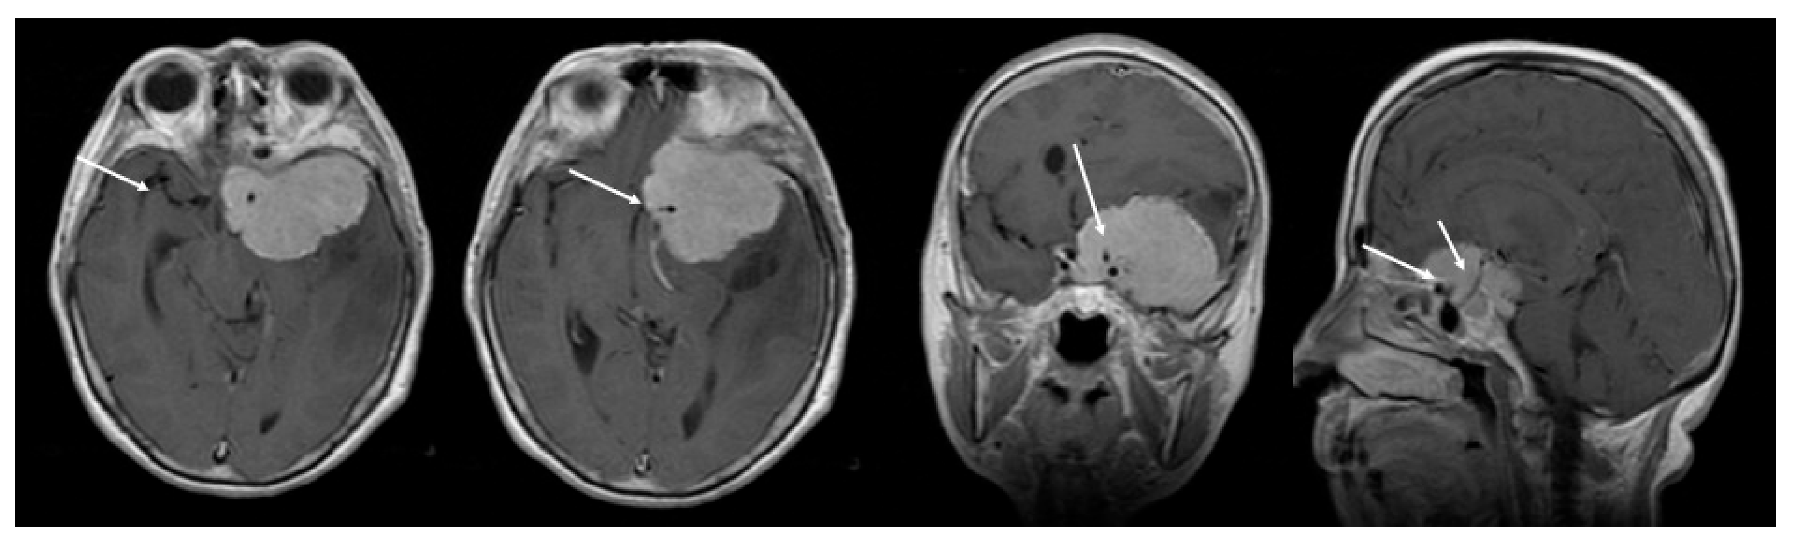

3.2. Preoperative Clinical and Radiological Data

3.3. Quality of Resection